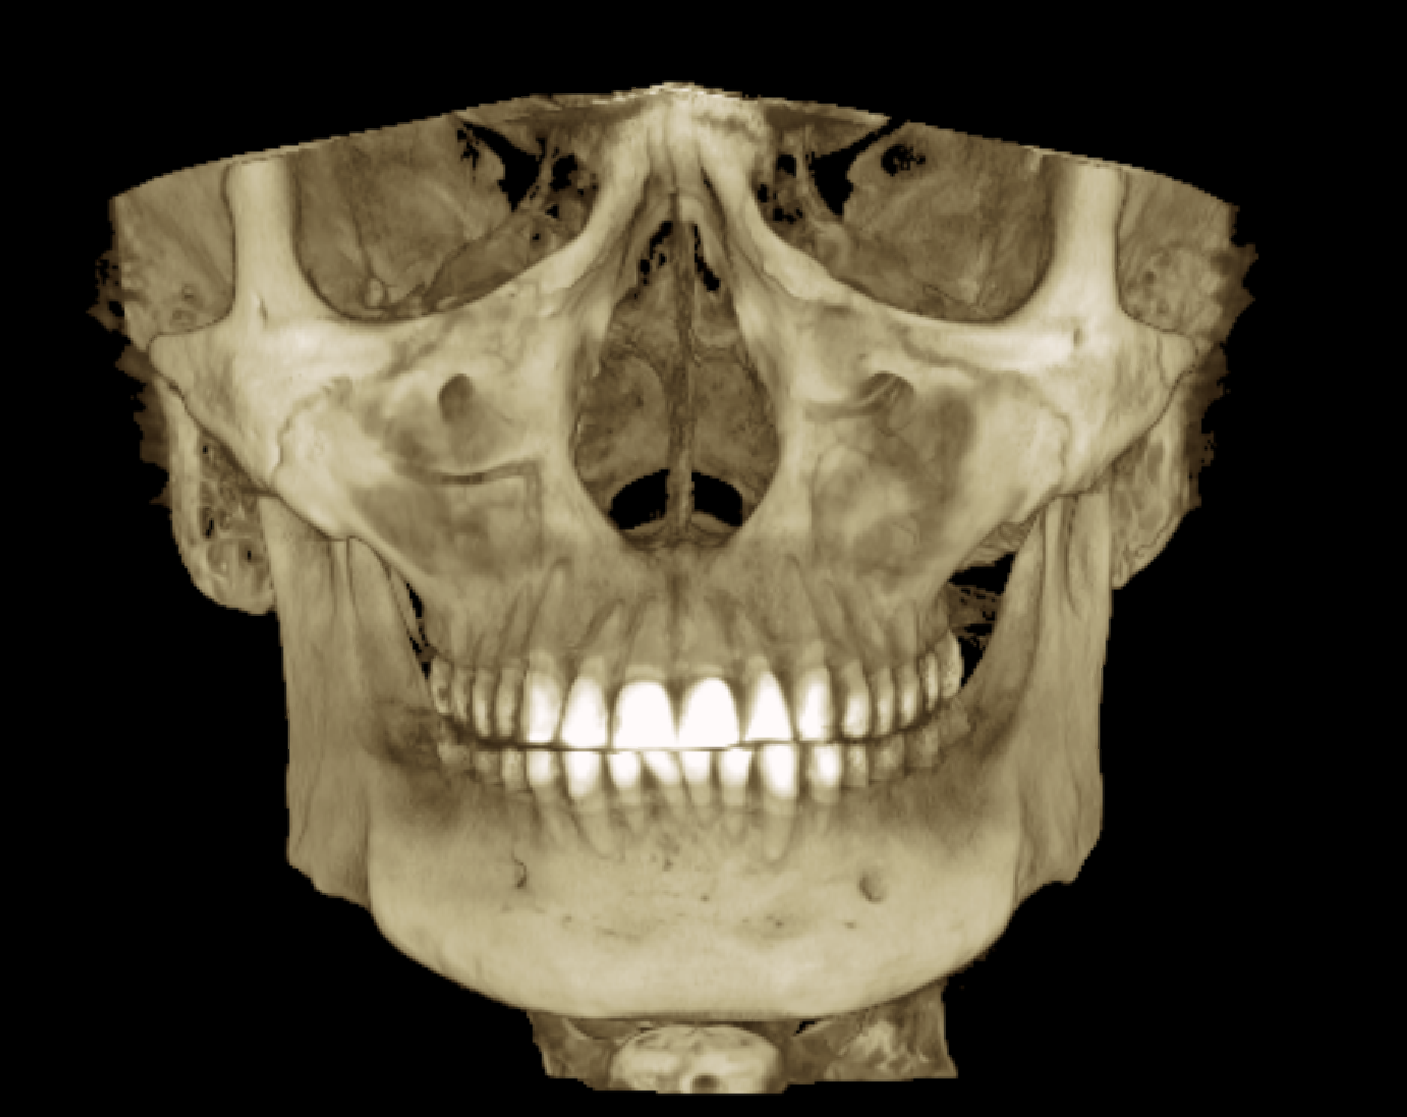

Сделал снимок своей челюсти, чтобы вам было лучше видно какой я унтерменш

>хуйло с дистальным который без проблем вытягивается брекетами

мимо хуйло с дистальным только операция ценой 1.5кк+

>>331338129 (OP)

изимодник с идеальными зубами чтоб ты сдох

ищо и денег есть на такой рентген, он тыщ 20 стоит наверняка